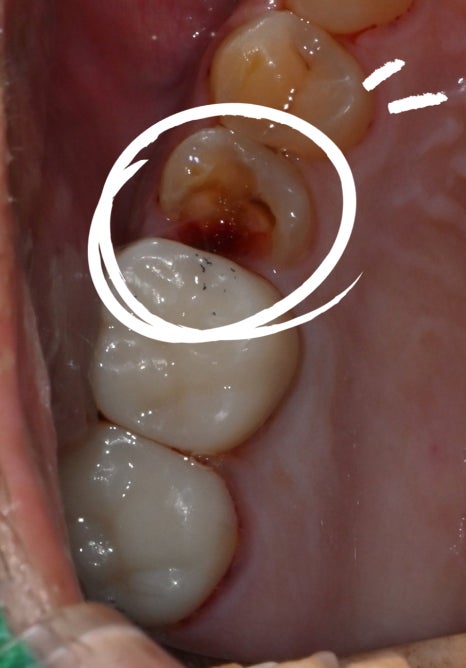

<치료 전 / 치료 후>

그리고 어금니는 힘을 많이 받는 부위라

신경치료 후에는 꼭 크라운으로 씌워서 보호해줘야 해요.

마지막은 지르코니아 크라운으로 단단하게 마무리

신경치료까지 끝나면 마지막은

지르코니아 크라운으로 마무리합니다.